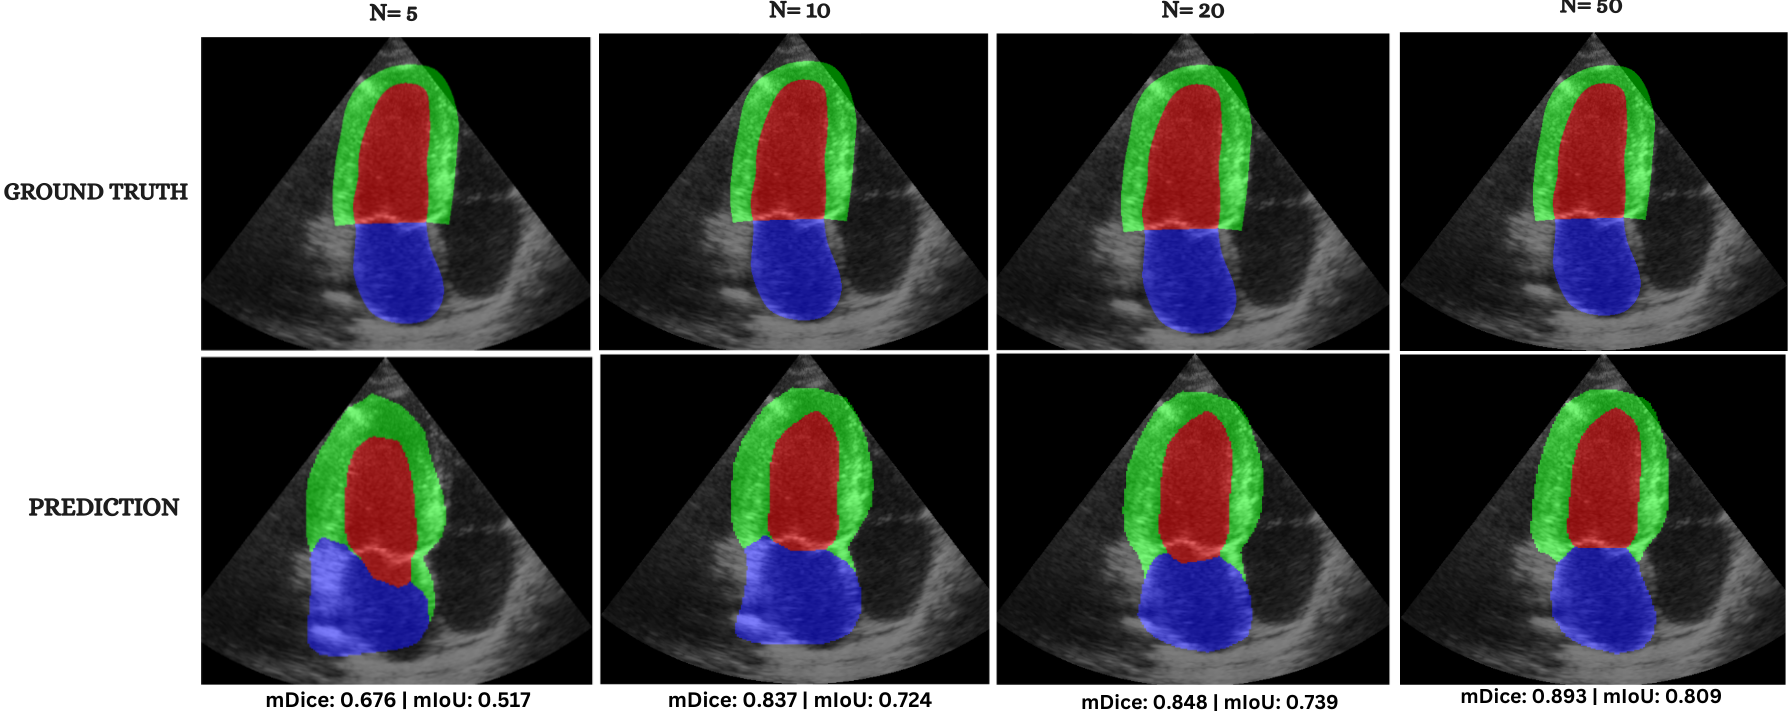

4.9 Few Shot Cross Modality Adaptation (CAMUS)

To evaluate whether PULSE generalizes beyond MRI, we conduct a few-shot transfer study using the CAMUS echocardiography dataset. Unlike cine-MRI, ultrasound introduces significant domain shift due to speckle noise, limited field-of-view, and weaker boundary contrast. We fine-tune the ACDC trained model using only labelled subjects and evaluate on the remaining scans. Results are reported in Table 12. Performance increases monotonically with the number of available samples, indicating that the model retains MRI learned anatomical priors and adapts efficiently to ultrasound geometry. With only five labelled cases, the model preserves reasonable ventricular delineation (0.612 mean Dice) and improves steadily to 0.815 Dice with 50 cases, as shown in Fig 5. Right ventricular segmentation benefits the most from supervision, rising from 0.749 to 0.880 Dice, while myocardium improves gradually due to noisy wall boundaries inherent in echo. Beyond quantitative improvement, the few shot behaviour of PULSE is clinically meaningful. Hospitals, especially those in regions with limited imaging infrastructure, rarely have large labeled datasets for model adaptation. The ability to reach a mean Dice of 0.815 using only 50 CAMUS subjects and remain functional even with as few as five suggests that the model can be deployed rapidly in settings where annotation is expensive, time restricted or performed by a single specialist. In practice, this means that a centre acquiring a small number of local scans could calibrate the system to their scanner characteristics and patient population without requiring a full retraining cycle.

To evaluate cross–modality transfer, we perform few–shot fine tuning on the CAMUS echocardiography dataset, using only {5, 10, 20, 50} labeled samples from a single clinical site. Unlike MRI, ultrasound poses a significantly harder segmentation challenge due to acoustic artifacts, speckle noise, anisotropic contrast, and view–dependent anatomical deformation. Despite this domain gap, Figure 10 shows that PULSE progressively adapts to ultrasound geometry with increasing supervision. With only 5 labeled cases, the model produces coarse chamber boundaries and myocardium leakage, yet still recovers the global cardiac shape (mDice 0.612, mIoU 0.468). At 10 samples, segmentation accuracy improves substantially, with clear endocardial delineation and reduced basal drift (mDice 0.696, mIoU 0.556). Fine tuning on 20 cases leads to stable myocardium recovery (mDice 0.746), suggesting that the model internalizes modality–invariant structure once minimal supervision is available. At 50 cases, performance reaches near–MRI quality (mDice 0.815, mIoU 0.705), approaching full–data performance and producing visually crisp LV and RV walls even under ultrasound noise. These results demonstrate that PULSE can retain cardiac anatomical priors learned from MRI and rapidly transfer them to ultrasound with very limited supervisiona desirable property for deployment in low resource hospitals where complete annotation is rarely available. The smooth improvement across shots also reinforces the quantitative trend of Table 12, validating few–shot echocardiographic adaptation as a viable clinical pathway for real-world integration into emergency, bedside, and limited–annotation scenarios.